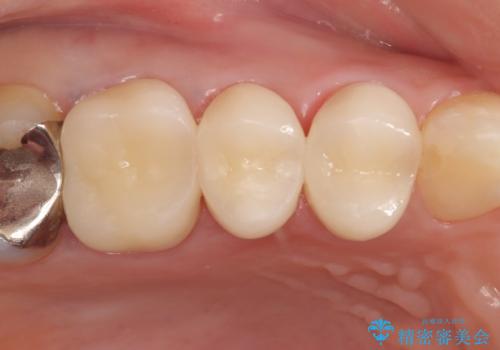

今回用いたオールセラミッククラウンはジルコニアフレームという白い素材の上にセラミックを盛っているため、審美性が非常に高いのが特徴です。

また、ジルコニアは人工ダイヤモンドの材料にも使われているほど高い強度を持っており、そのためオールセラミッククラウンは審美性だけでなく、奥歯やブリッジの補綴も可能とするクラウンです。